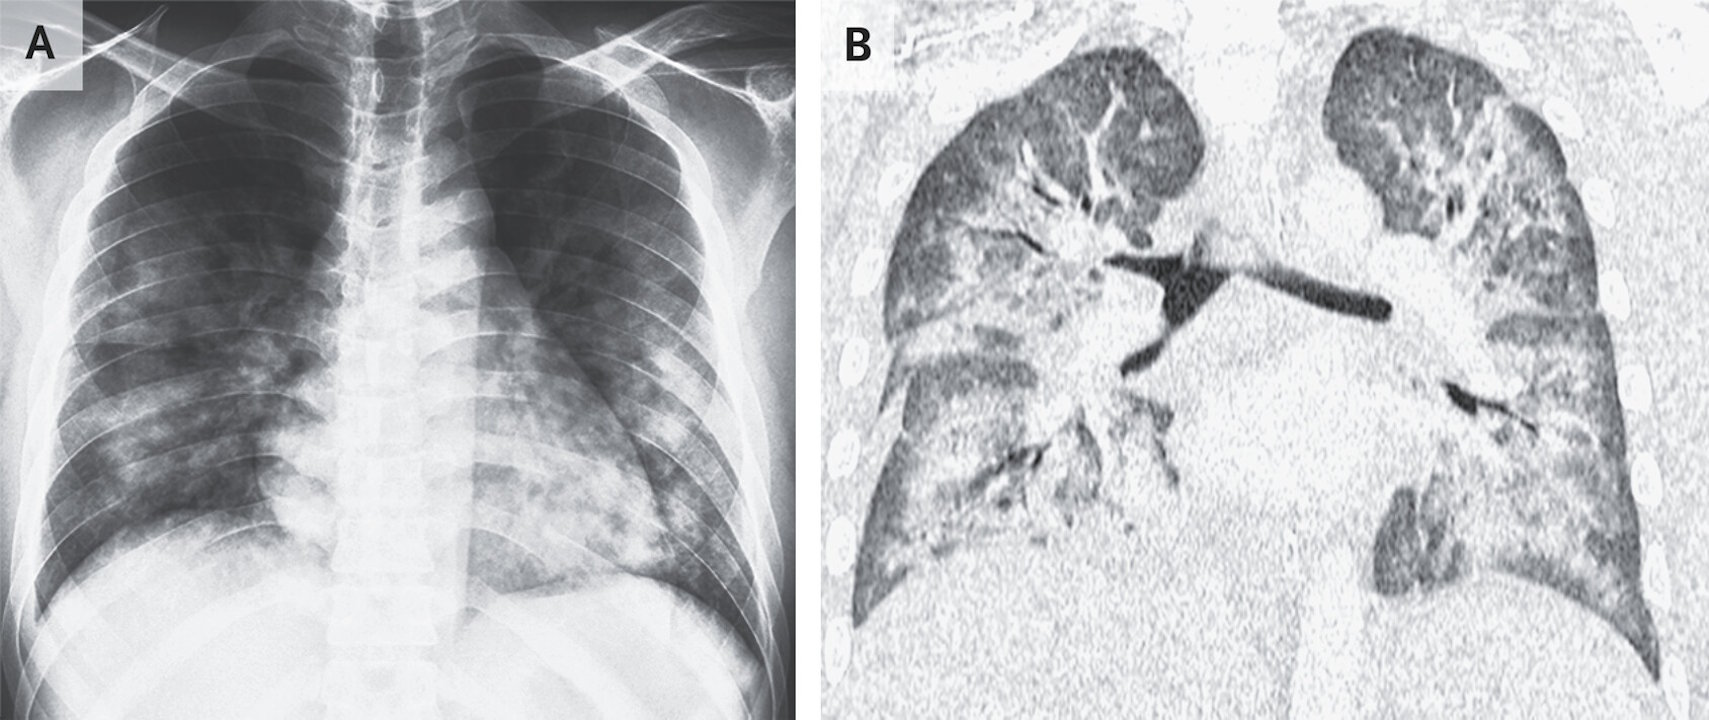

Світлі плями на легенях хлопця — сліди ушкоджень тканин через паління електронних сигарет (зліва — рентгенівський знімок, справа — комп'ютерна томографія). Zulkimi Roslly & Syed Rozhan / The New England Journal of Medicine, 2025

Обстеження показало, що він мав частоту дихання 44 вдихи на хвилину за норми 12-24 вдихи. При цьому кров хлопця була насичена киснем лише на 83 відсотки, а в обох легенях прослуховувалися хрипи. Під час комп’ютерної томографії легень у нього виявили рідину між легенями та їхньою оболонкою, однак у зразку цієї рідини медики не виявили збудників хвороб, які могли б спричинити симптоми хлопця.